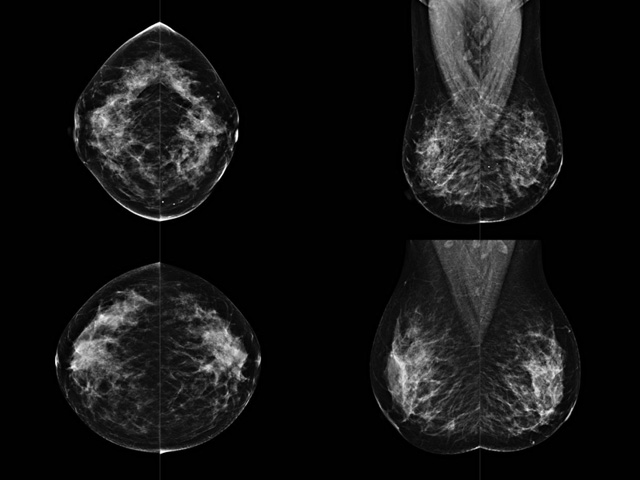

乳房檢查時(shí)候要注意一些細(xì)節(jié),需要更深入的了解這樣才能使檢查更準(zhǔn)確。乳腺DR是乳腺癌的篩查診斷工具設(shè)備。是乳房方面檢查的重要影像方法。它可以臨床檢查出早期的乳腺癌??梢耘袛嗔夹詯盒?。因?yàn)樗梢詸z查出早期的病變。對(duì)良性惡性檢查的準(zhǔn)確率達(dá)到90%以上。發(fā)病高峰年齡為45歲到54歲。50歲檢查出來乳腺癌病患,可以讓死亡率下降3成。所以30-40歲女性每年做一次乳腺DR檢查。40歲以上就一年兩次。如果家族史有乳腺癌的30歲以下也需要做檢查。清晰顯示乳腺各層組織嚴(yán)重的乳腺增生,乳腺炎,乳腺外傷也建議1年檢查一次。極大提高了早期乳腺癌的敏感度和診斷率。

大角度、高質(zhì)量的乳腺檢查,可以讓女性帶來身體健康安全。為醫(yī)生提供了高清影像數(shù)據(jù)。乳腺檢查時(shí)候各個(gè)部位影像顯示出來。白色乳腺導(dǎo)管跟纖維結(jié)締組織。模糊的是脂肪。病變一般是不透明的白色。有需要放大來檢查。乳腺DR沒有重疊偽影。輻射劑量更少。因?yàn)槿橄侔┌l(fā)病每年都有所提高,對(duì)女性都造成了嚴(yán)重的身體健康危害。早做檢查早治療是不可忽視的舉措??梢源蟠蟮慕档?/span>死亡率。保證身體健康。一般檢查避開經(jīng)期,來完7天左右是最佳的檢查時(shí)間。絕經(jīng)的女性就沒有要求。孕婦不參加乳腺DR檢查, 6個(gè)月內(nèi)準(zhǔn)備妊娠的婦女也不宜行此檢查。